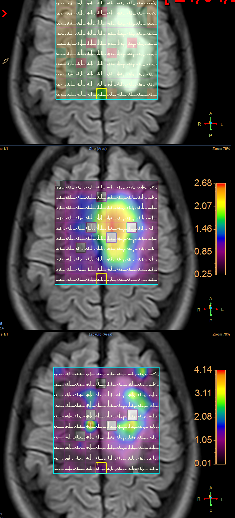

Fig3a,b – Espectroscopia de Múltiplos Voxels (EMV) em caso de glioma de alto grau (Astrocitoma anaplásico – III) frontal esquerdo. Traçados de mini voxels colocados no interior e no tecido cerebral vizinho (a, b), para avaliar grau de invasividade tumoral mostram níveis elevados de cholina dentro e fora da lesão.

Fig3c,d – Espectroscopia de Múltiplos Voxels (EMV) em caso de glioma de alto grau (Astrocitoma anaplásico – III) frontal para sagital esquerdo. Traçados de mini voxels colocados no interior e no tecido cerebral vizinho para avaliar grau de invasividade tumoral mostram níveis elevados de cholina dentro e fora da lesão redução do NAA (c) e acúmulo de lactato(d).

A figura acima apresenta mapa de metabólitos (cholina e NAA) que mostram redução de NAA por substituição de tecido normal por células neoplásicas e acúmulo de cholina por proliferação celular glial (c). Também o mapa de metabólitos (cholina e lactato), mostra, além de acúmulo de cholina, a presença de lactato, inferindo hipóxia intratumoral (d).